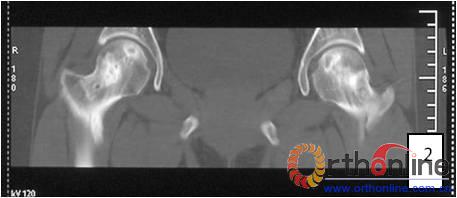

病灶修复情况比较,加用BMP2组病灶修复的完全性及硬化骨数量普遍优于未加BMP2组。(图3)

图3-1 女,31岁,SARS患者骨坏死,(1)MRI示双侧股骨头坏死,右Ⅱb(B型),左Ⅱc(C1型);(2)打压植骨术(未加BMP2)后坏死修复不完全,仍遗留股骨头软骨下病灶未完全修复, 5年随访关节功能优(Harris评分96分)